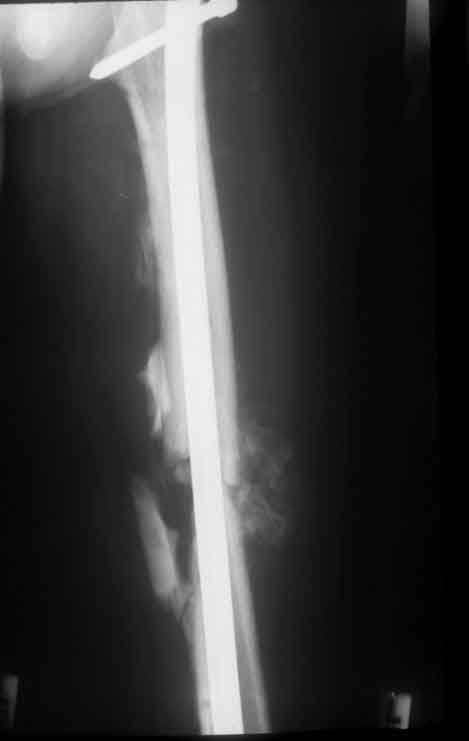

Rö.Bild vor und nach der Stabilisierung mit Hoffmann 2 Fixateur in der "free Pin-.placement" Technik.

Stabilisierung mit V-Nagel nach Besserung des Allgemeinzustandes am 12. postoperativen Tag.